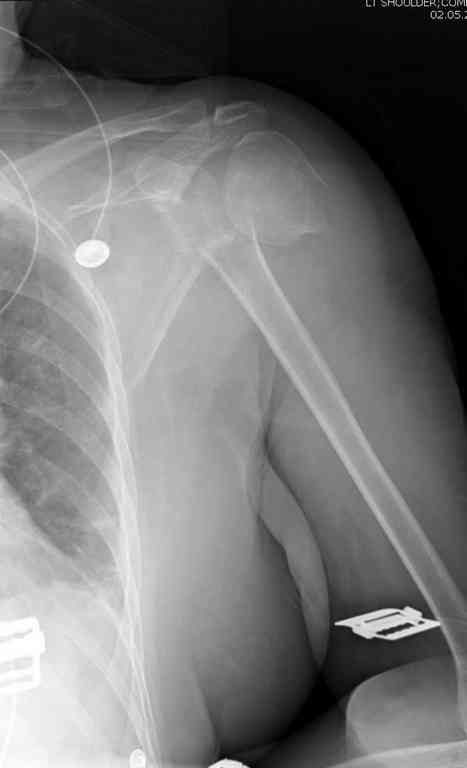

> Боковой снимок нормально не сделать, вторая проекция сделана под углом 30 градусов.

Вполне нормальный и читаемый снимок - лопаточная или Y проекция входит в "травма-серию" плечевого сустава как стандарт.

Относительно контрольного КТ - впечатление такое, что малость перестарались при репозиции.

Оставлять такой диастаз пожалуй нежелательно. Мы бы вправляли закрыто и фиксирoвали спицами через головку в диафиз - в большинстве случаев получалось неплохо, тем более - перелом вроде двухфрагментарный. ЭОП-контроль на столе - если что-то не так - ORIF.